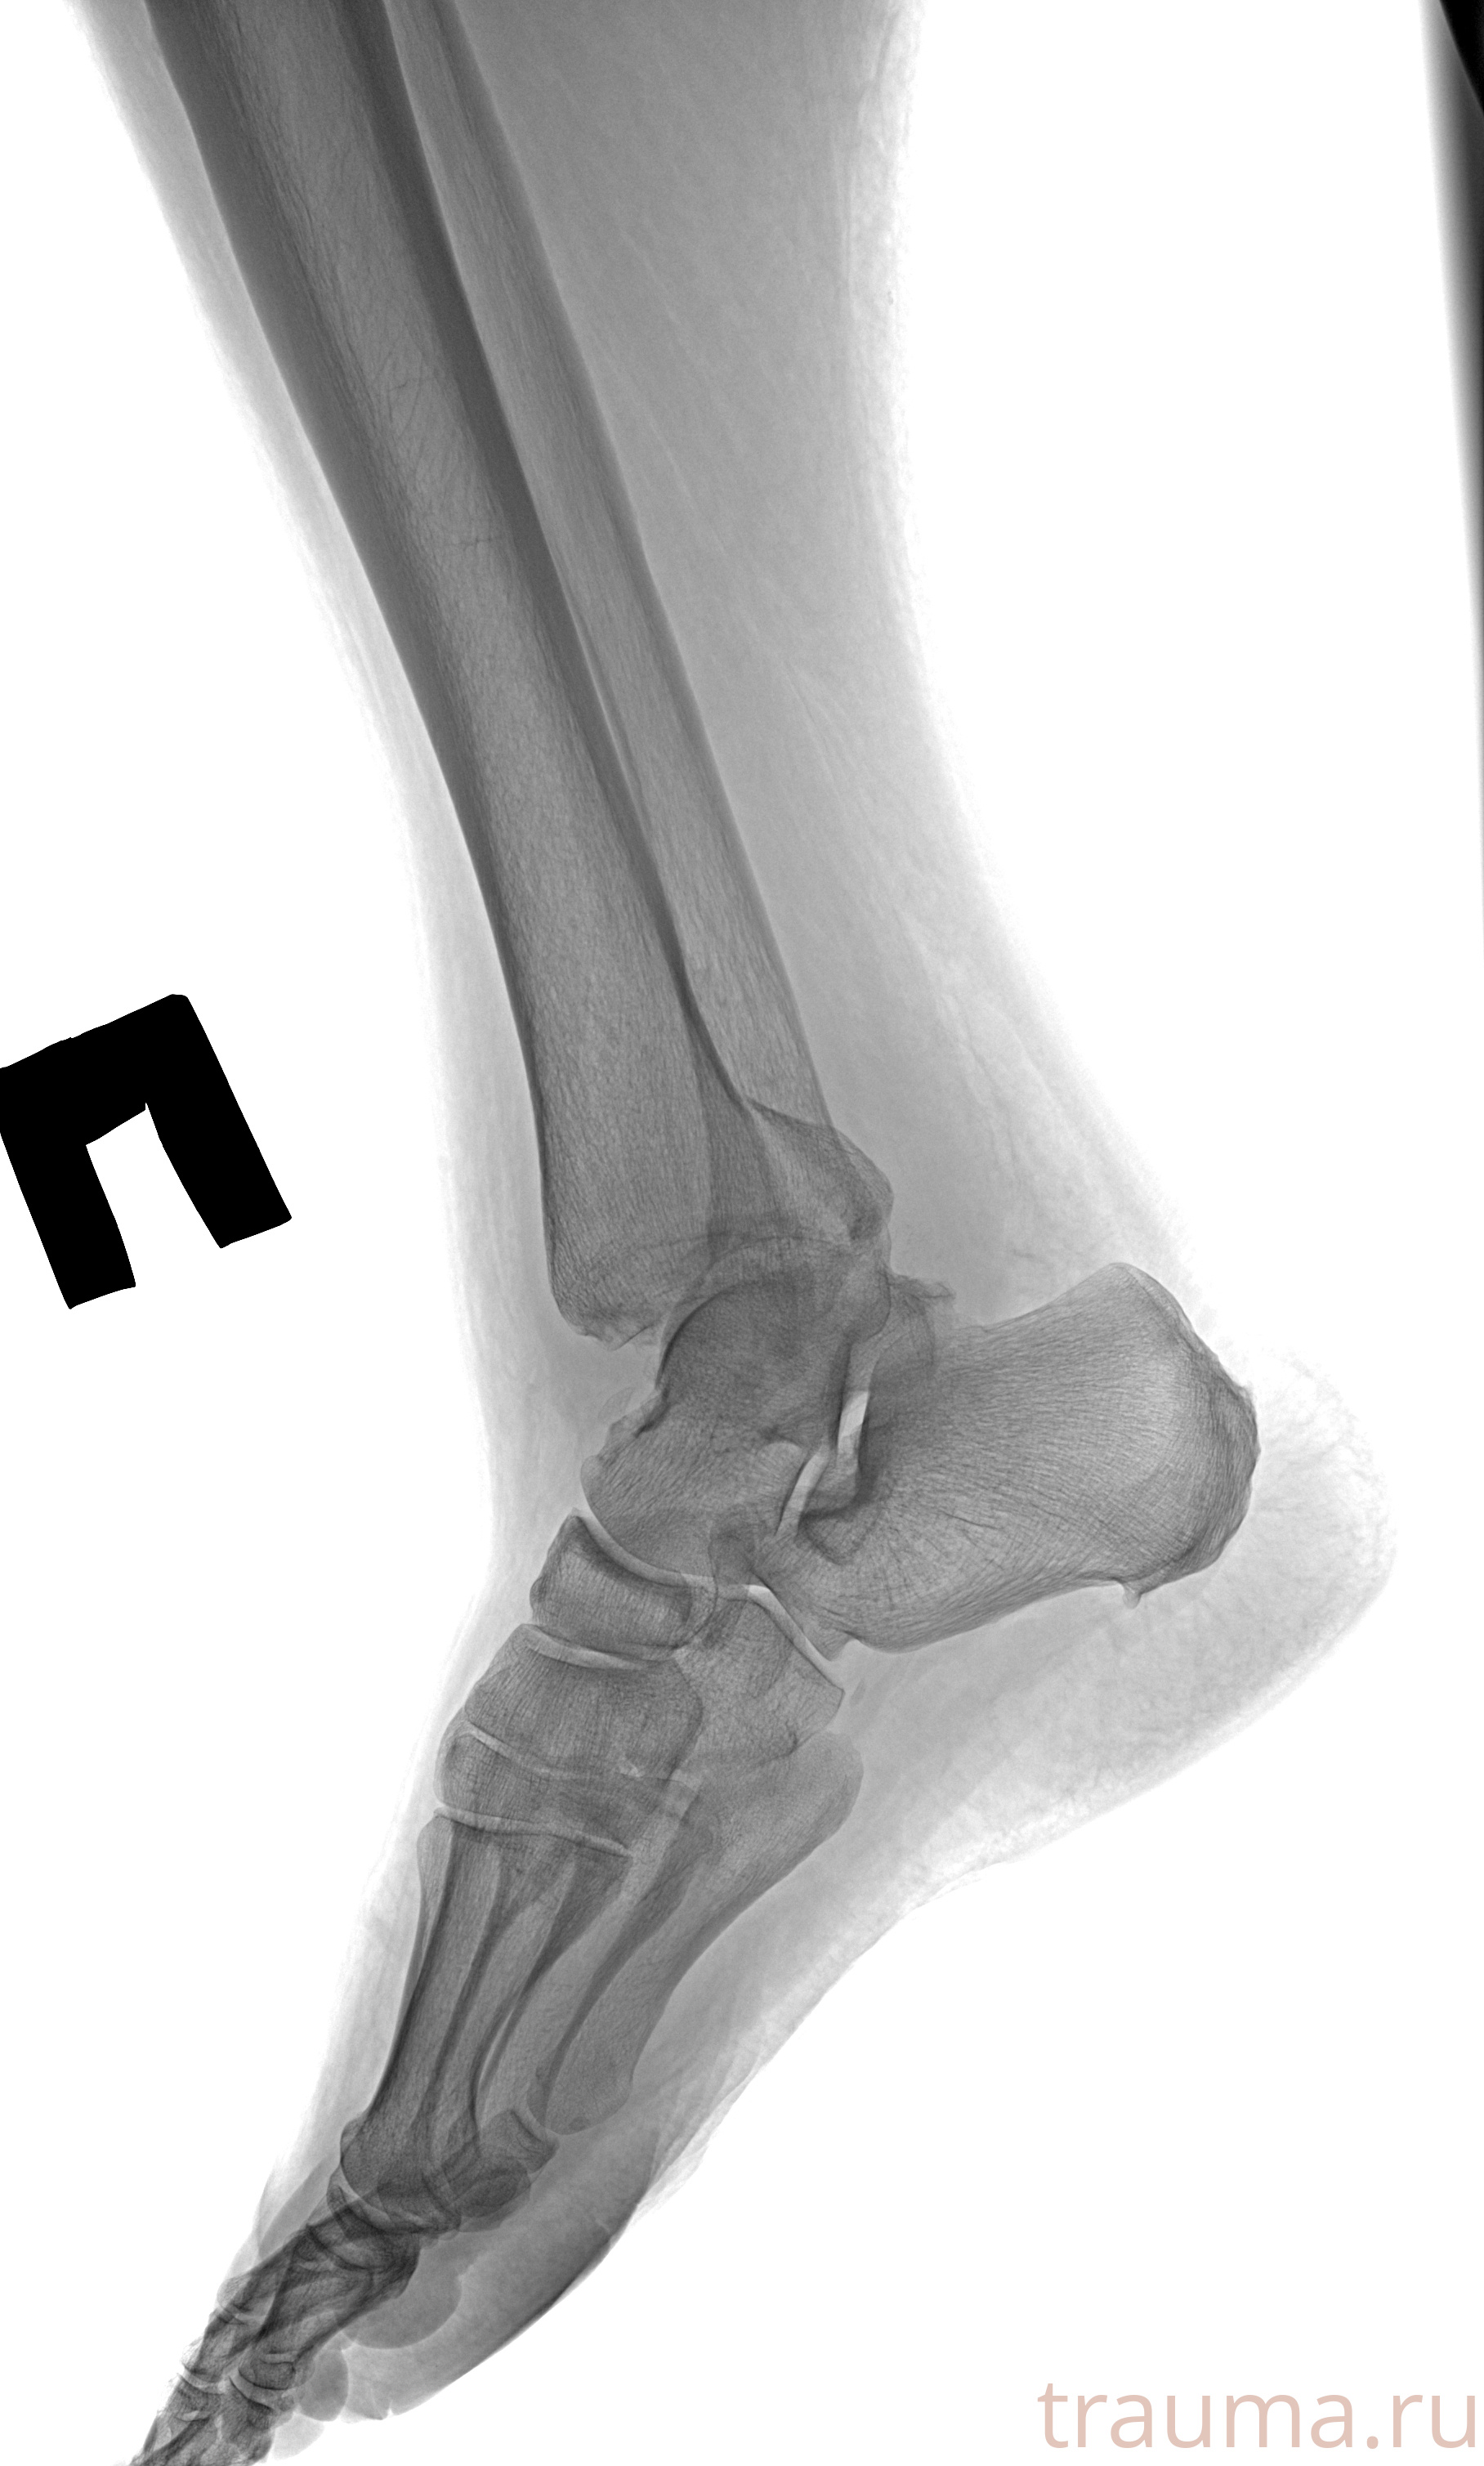

Рентгенограммы

Рентген на дому: по вашему адресу приезжает врач-рентгенолог, травматолог-ортопед с мобильным рентгеновским аппаратом, проводит диагностику травмы или заболевания, делает необходимые рентгенограммы, дает рекомендации по дальнейшему лечению. Получить качественные снимки в домашних условиях возможно благодаря уникальной методике, разработанной МосРентген Центром для института  Склифосовского